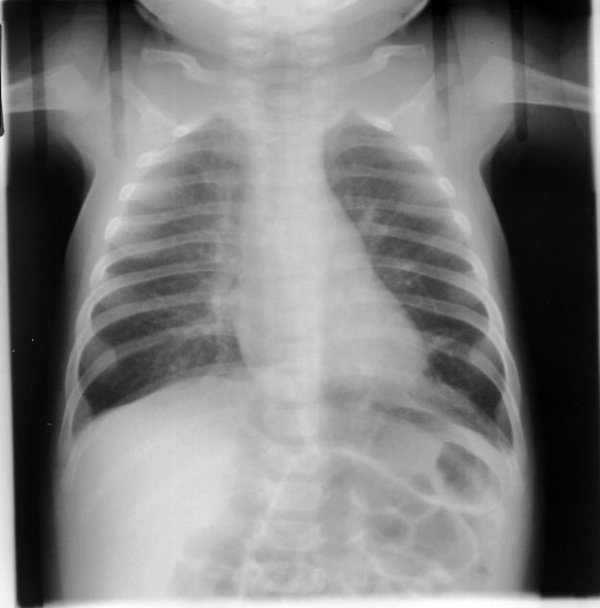

What is going on in this infant’s radiograph?

There is hyperinflation and increased perivascular markings. It can be fairly subtle, the perivascular markings are the biggets tell. Sometimes complete RUL collapse is observed.

On the lateral radiograph associated with this case you can better appreciate the hyperinflation via the flattening of the diaphragm.

In the right clinical context, this is suggestive of bronchiolitis, particularly RSV.